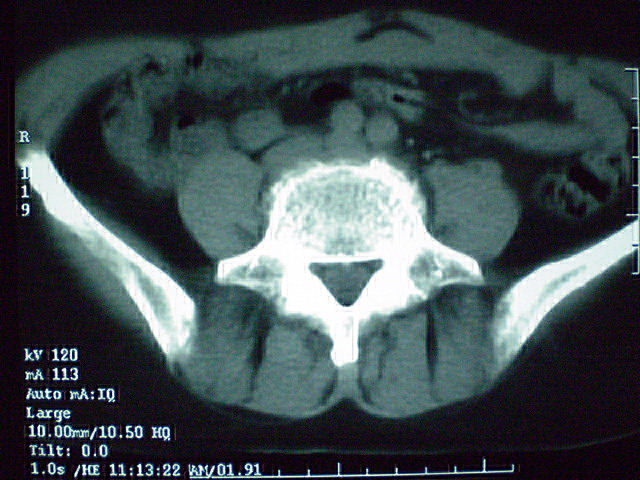

f 60y,b超提示脂肪瘤.[img][/img]

右侧附件囊性畸胎瘤,三种组织均见.

那个高密度灶形状好象牙齿。典型,收藏了

脂肪密度肿块,内可见团块状影,典型皮样囊肿

的确比较典型的畸胎瘤!不过,应该确切的说是盆腔畸胎瘤,右侧附件来源的可能性比较大。

有钙化,畸胎瘤